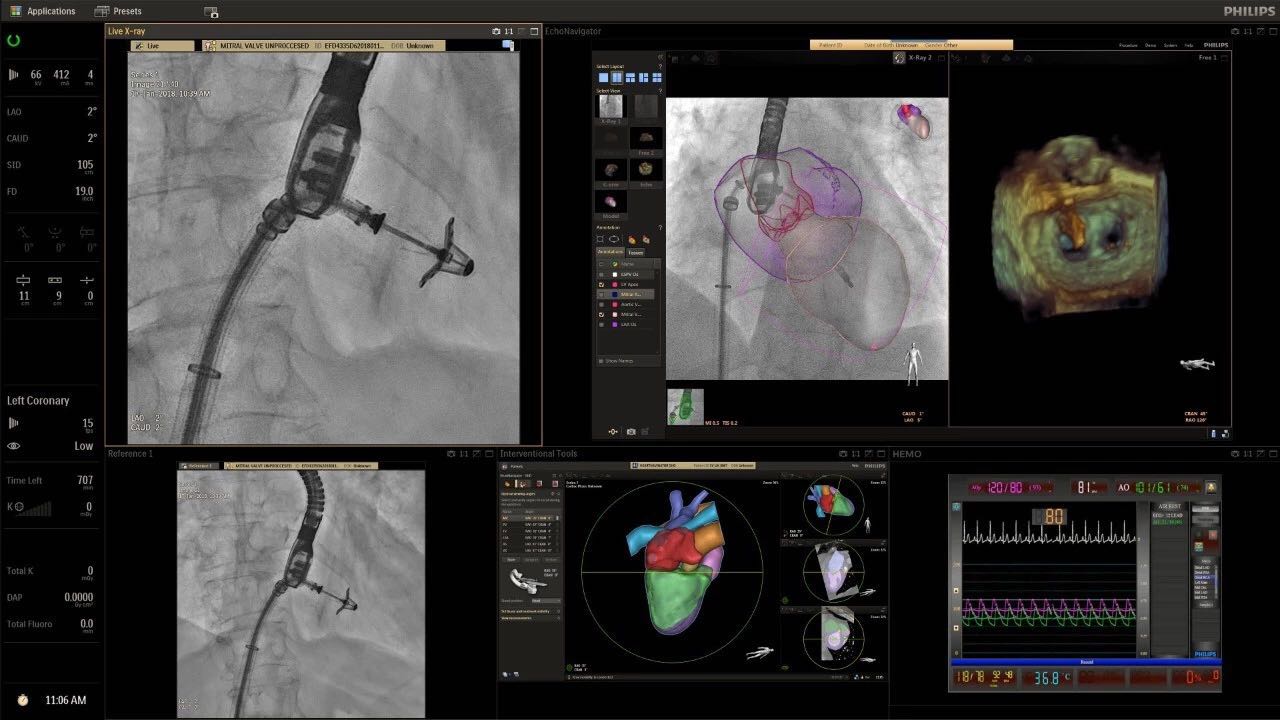

在日益復(fù)雜的干預(yù)期間,臨床醫(yī)生需要快速、輕松地可視化關(guān)鍵解剖結(jié)構(gòu)并確定手術(shù)過程中患者的變化。2019年1月17日,飛利浦宣布推出采用FlexArm的Azurion 7 C20,旨在提高圖像引導(dǎo)程序的定位靈活性。

帶有FlexArm的Azurion 7 C20 包含一系列創(chuàng)新技術(shù),使臨床醫(yī)生可以更輕松地在整個患者身上進(jìn)行二維和三維成像。當(dāng)臨床醫(yī)生移動系統(tǒng)時,圖像光束自動保持與患者的對準(zhǔn),允許更一致的可視化并使他們能夠?qū)⒆⒁饬性谥委熒稀?/span>

(FlexArm C型臂可以沿著工作臺的兩側(cè)提供偏心成像。這允許醫(yī)生在左臂或右臂上進(jìn)行徑向進(jìn)入病例,完全或部分伸展,而無需移動患者或樞轉(zhuǎn)桌子。X射線束與手臂保持對齊,以促進(jìn)其整個長度的平滑導(dǎo)航,而無需進(jìn)行持續(xù)調(diào)整。)

飛利浦表示,采用FlexArm設(shè)計(jì)的Azurion 7 C20可提供卓越的靈活性和直觀的控制。該系統(tǒng)由智能運(yùn)動引擎驅(qū)動,可在八個不同的軸上移動,所有這些軸均由其單個“Axsys”控制器控制。臨床醫(yī)生的模擬測試表明,該系統(tǒng)有可能顯著減少患者,工作人員和設(shè)備的重新定位,從而改善微創(chuàng)手術(shù)的可及性,包括通過患者手腕進(jìn)入身體的手術(shù)(橈動脈入路),并降低患者的風(fēng)險(xiǎn)。無意中拔出電線和管子,以及節(jié)省大量時間。該系統(tǒng)非常適合混合手術(shù)室(OR),可滿足一個房間內(nèi)的多種專業(yè)需求,例如手術(shù)和血管內(nèi)手術(shù)的組合。

(FlexArm在不少于8軸的情況下旋轉(zhuǎn),從而創(chuàng)建幾乎無限的靈活性來執(zhí)行成像,從頭部到腳部在左側(cè)和右側(cè)進(jìn)行2D和3D可視化。圖像光束保持與患者對齊,允許在旋轉(zhuǎn)或角度期間更好地可視化解剖結(jié)構(gòu)。使用Axsys運(yùn)動控制系統(tǒng)輕松操作支架。)